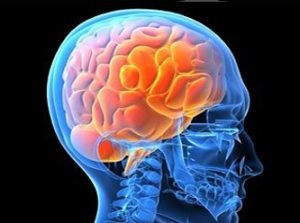

Megsértése agyi keringés

- szívbetegség;

- helyi értágulat;

- növelése shchitovidki;

- légzőszervi betegségek;

- tumorok a nyak;

- fejsérülések;

- folyadék felgyülemlése az agyban;

- vérrögök a vénákban.

- gyakori fejfájás, amelyek fokozni fej mozgása;

- vénák a fundus;

- vénás nyomás 50 és 80 Hgmm. Cikk.;

- érezte, hogy a zaj a fejemben;

- duzzanatokat a szem alatt;

- kék árnyalat a bőr;

- gyakori eszméletvesztés;

- zsibbadás kezek és lábak;

- A beteg fog zavart pszicho-emocionális alapon;

- ember lesz rosszabb, ha a vízszintes helyzetben a test és a fej mozgatásával le;

- a fájdalom erősebb lesz az alkoholfogyasztás és a stressz.

A kezelés alkalmazásával gyógyszerek egy vizelethajtó hatású, és a gyógyszerek, amelyek képesek csökkenteni a nyomást. Vannak olyan gyógyszerek, amelyek csökkenthetik a torlódások a vénákban. A jó hatás a masszázs után. A beteg csináld magad, masszírozó ujjak nyak, fej. Ezt fel lehet használni az elektromos áramlást a vénákban.

Vénás pangása a fej kell kezelni teljes körű vizsgálatot követően a beteg. Javítani kell a kimenetele kezelés, amely képes emberek jogorvoslatok, masszázs.